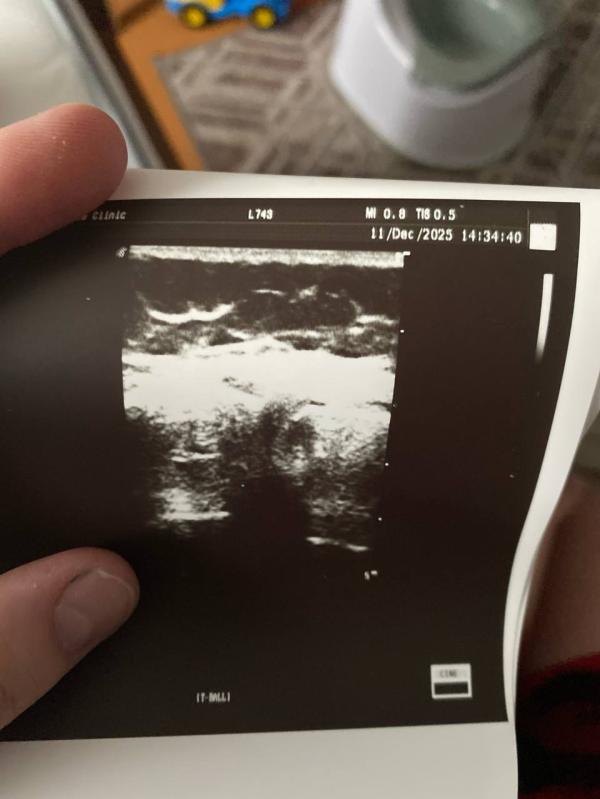

Ну что ж … сегодня была на узи коленного сустава…связки воспалены . Жидкости очень мало попадает в мениск… короче, колено болит невыносимо…